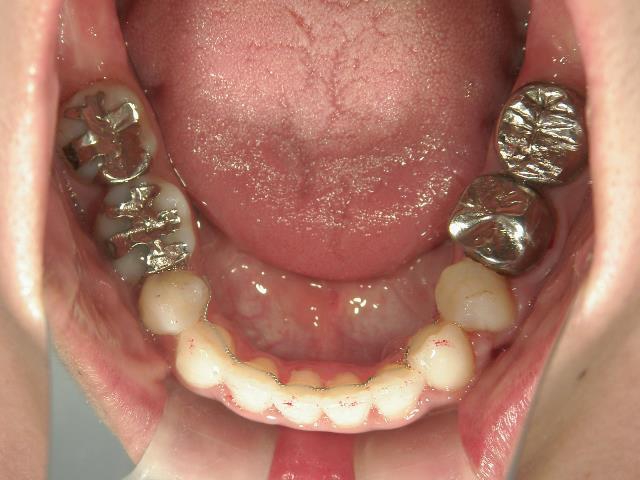

矯正歯科 治療後矯正歯科 全顎ワイヤー矯正 治療後矯正歯科(全顎ワイヤー矯正)治療後

矯正歯科 治療後

矯正_灰色.pngno.28_6958_治療後_下.jpg矯正_灰色.png